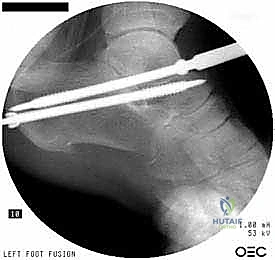

5. التثبيت الميكانيكي (Fixation)

بعد وضع العظام في الزاوية التشريحية الصحيحة تماماً، يتم تثبيتها بقوة لضمان عدم حركتها أثناء فترة الشفاء. يستخدم الدكتور هطيف مسامير ضغط كبيرة من التيتانيوم (Cannulated Screws). يتم إدخال هذه المسامير (عادة مسمارين) عبر عظم الكعب صعوداً إلى عظم الكاحل، وتعمل على ضغط العظمتين معاً بقوة هائلة، مما يوفر بيئة مثالية للاندماج.

6. إغلاق الجرح والجبيرة

بعد التأكد من وضع المسامير بشكل مثالي باستخدام جهاز الأشعة التداخلية (C-arm) داخل غرفة العمليات، يتم إغلاق الشق الجراحي بغرز تجميلية، وتوضع القدم في جبيرة خلفية مبطنة جيداً للحماية.